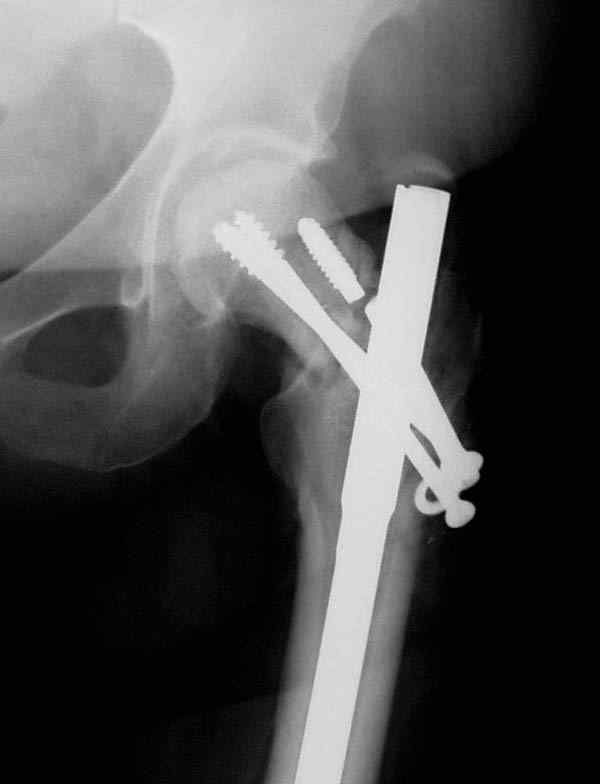

Одним из "золотых" правил при лечении переломов бедра в обязательном порядке до операции необходимо убедиться в отсутствии или наличии перелома шейки.

Отдельный снимок шейки или ЭОП является стандартом обследования. Все сомнительные рентген снимки проверяются тщательно дополнительными срезами КТ.

Из-за опасности вторичного смещения переломов "без смещения" во время интрамедуллярных манипуляций, особенно при ретроградном введении, необходимо каждый случай протоколировать с описанием состояния шейки после операции.

А не опорная болтающаяся конечность с большим рычагом усложнит состояние перелома шейки и поэтому ипсилатеральные переломы, тем более ятрогенные, очень часто осложняются двойными ложными суставами.